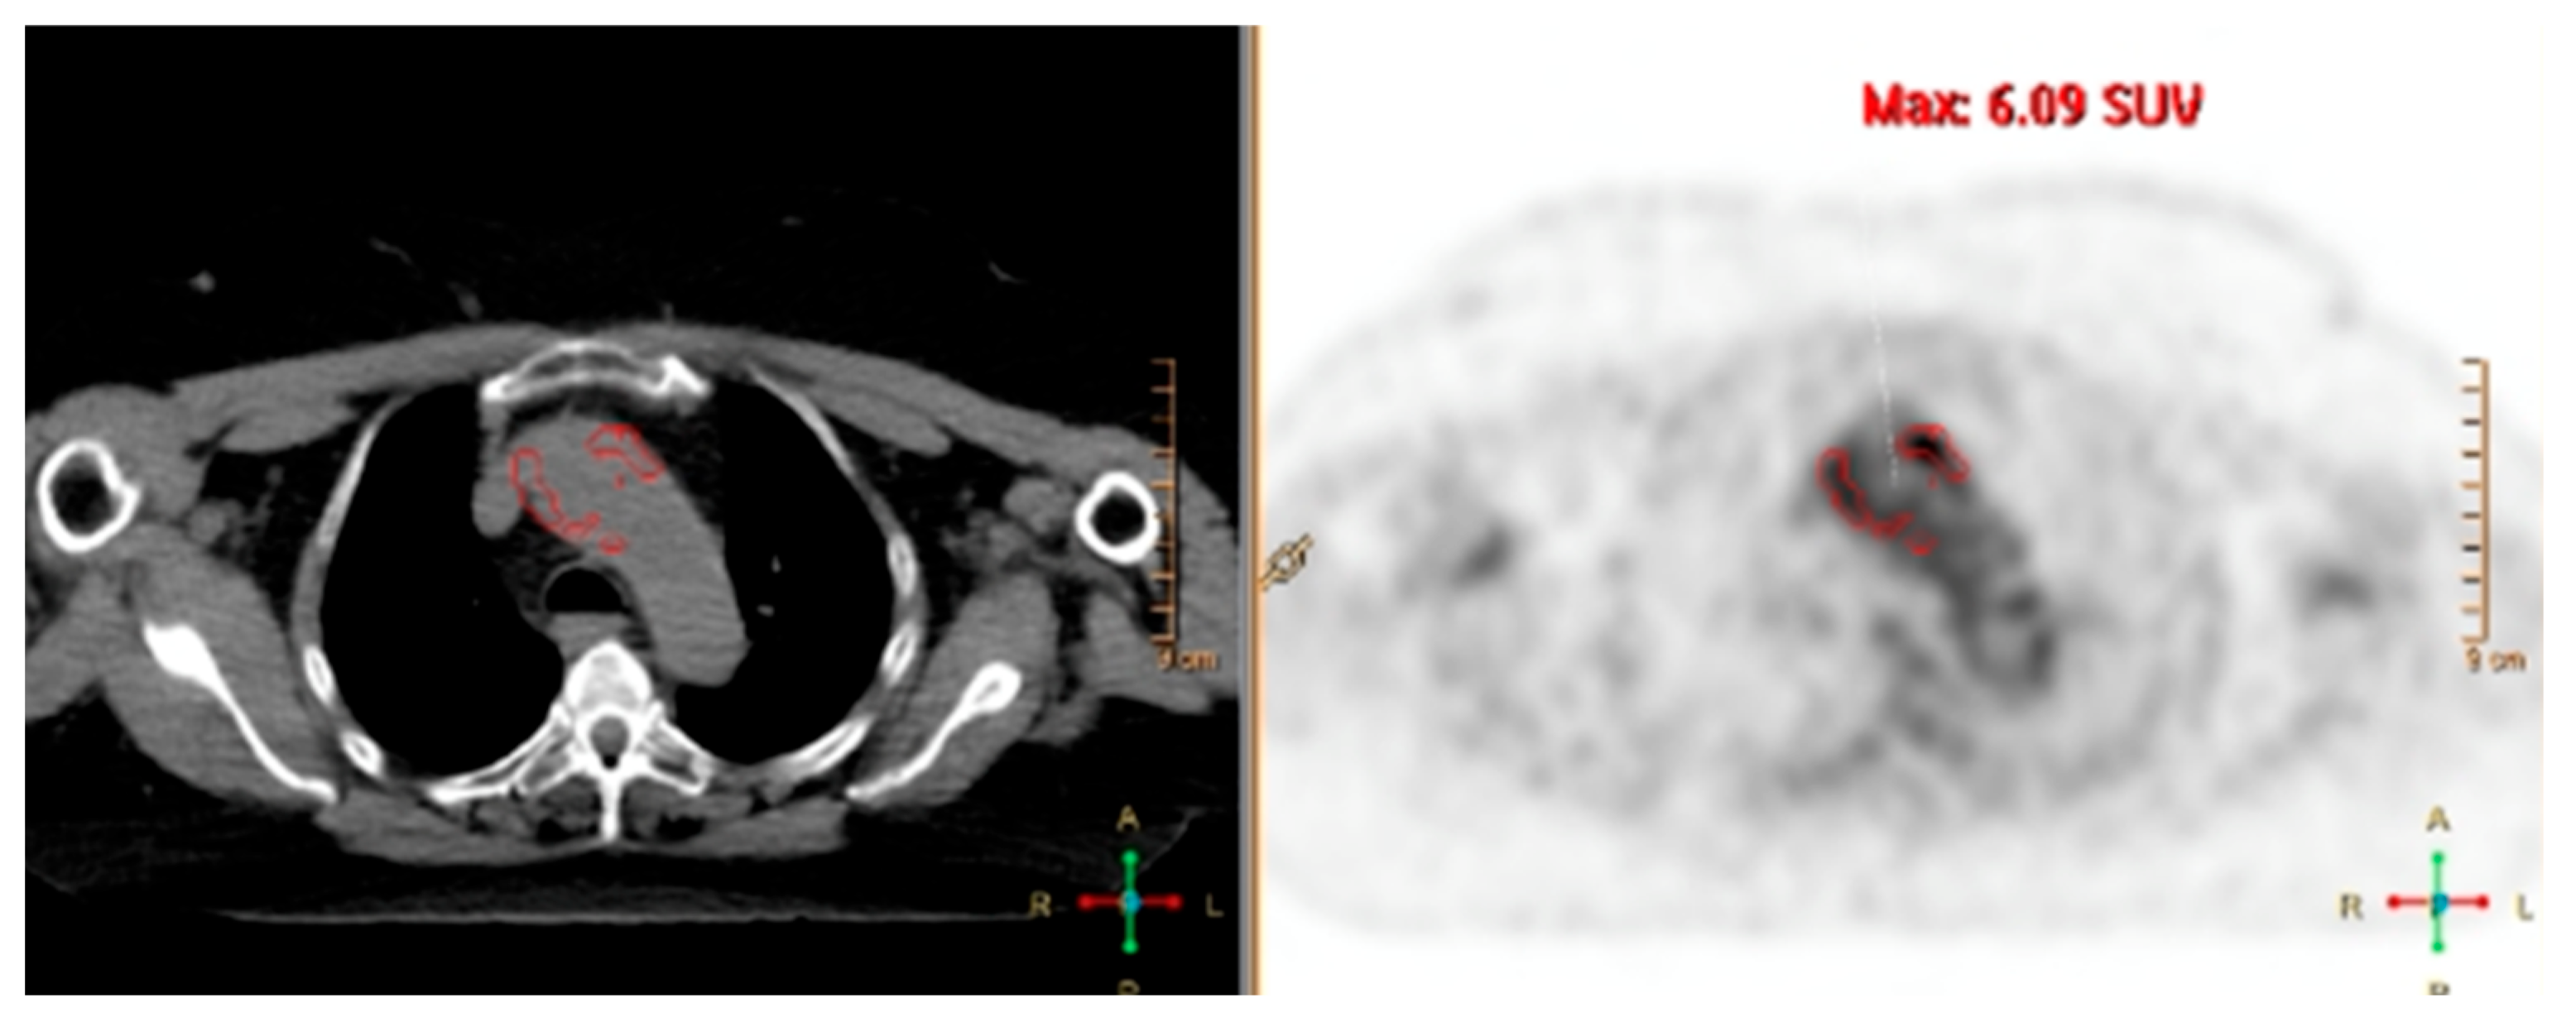

| FDG-PET/CT | Moderate; whole-body coverage. | High for active metabolic activity. | Sensitive to metabolic changes; useful for assessing treatment response. | Valuable in detecting relapse and for patients receiving IL-6 inhibitors. | Radiation exposure, high cost, limited availability, and low spatial resolution; limited sensitivity for vascular complications; uncertain significance of persistent or low-grade vascular uptake. |